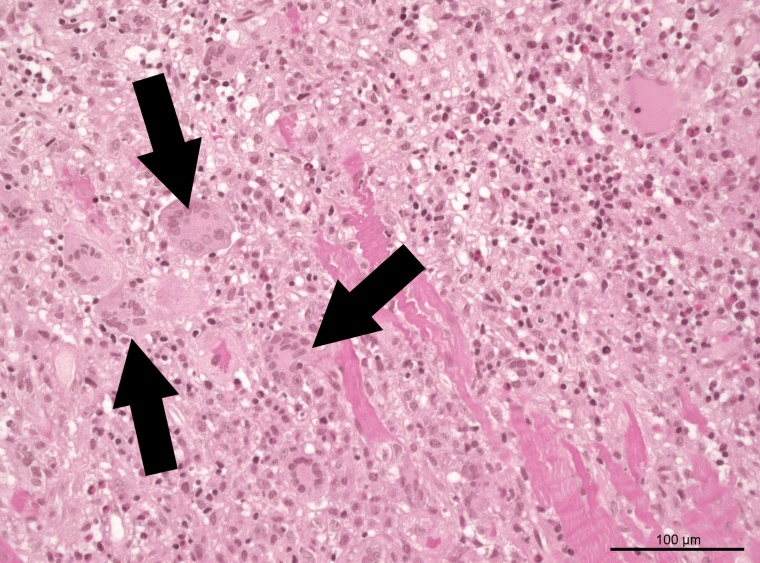

Eine erste wichtige Erkenntnis der Studie ist, dass Betroffene mit einer Riesenzellmyokarditis – eine Sonderform, die ihren Namen aufgrund sehr großer Zellen in den Gewebeproben trägt – eine deutlich höhere Sterblichkeit aufweisen (50 Prozent), als andere Untergruppen (circa 30 Prozent). Diese Daten weisen auf die große Bedeutung der frühen Gewebeentnahme zur Probengewinnung als einen zentralen Aspekt der Diagnostik der fulminanten Myokarditis hin.